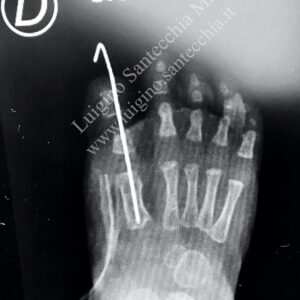

Before Surgical treatment